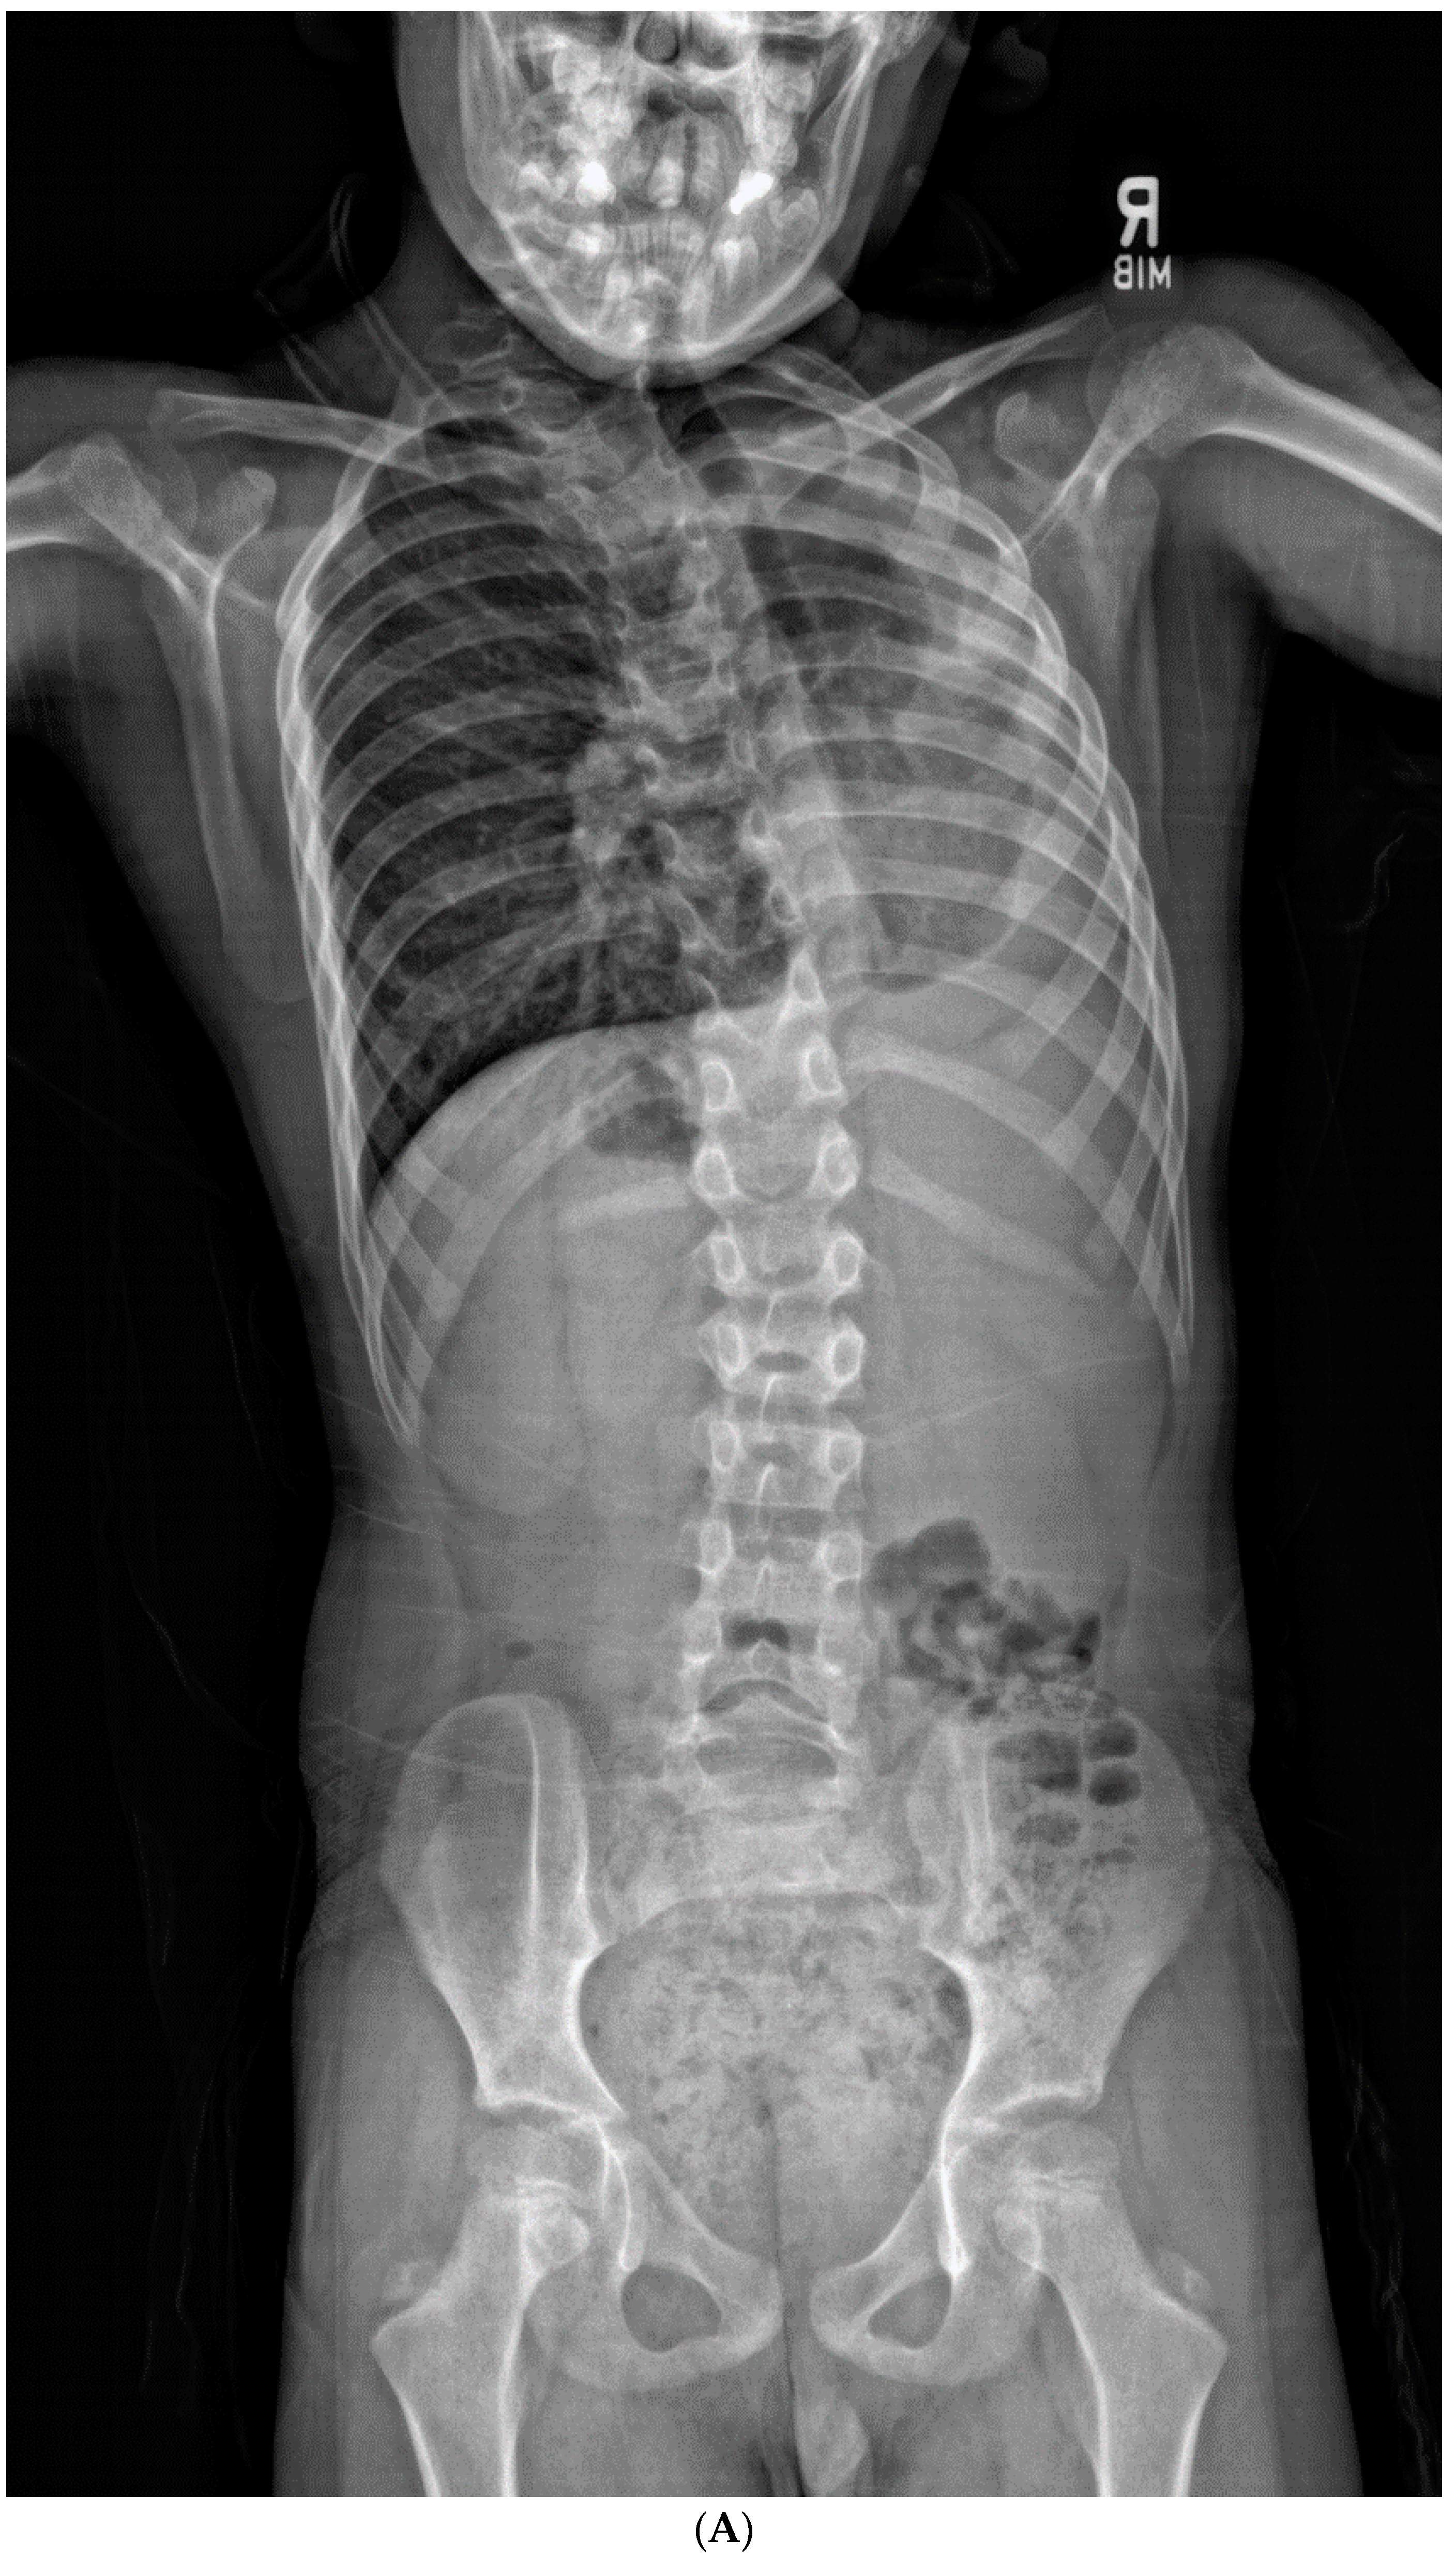

Risk Factors for Progression of Cervical Congenital Scoliosis and Associated Compensatory Curve Behavior

3. Results